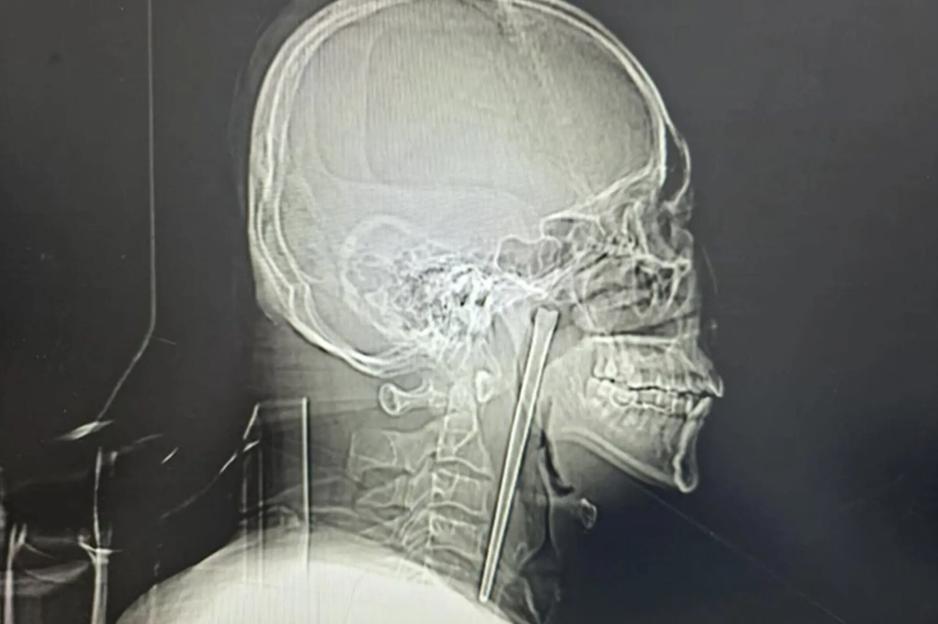

The chopstick was firmly lodged into the man’s throat for eight years Credit: CTS News/Youtube

A surgeon finally pulled out the five inch long metal rod from the man’s mouth last month Credit: CTS News/Youtube